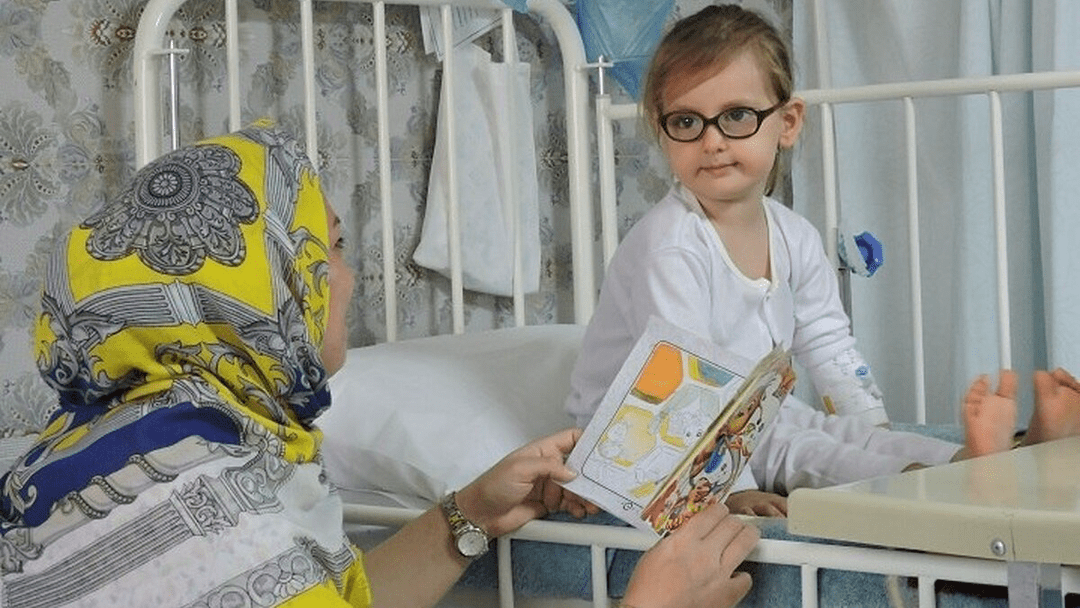

تخصیص 130 پزشک عمومی به دانشگاههای علوم پزشکی برای خدمترسانی به مجروحان